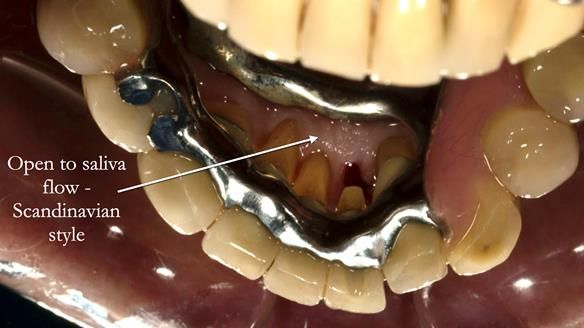

Instead, we made a Scandinavian-style, metal-based lower RPD.

The upper jaw

In the upper arch:

- a failing upper left tooth supporting a bridge was removed

- an implant-supported bridge on the upper right was dismantled

A metal-based upper RPD was made,

with metal backings incorporated to future-proof the design

should further teeth fail.

Scandinavian metal-based RPDs:

- support compromised teeth

- reduce the risk of fracture

- allow predictable addition of teeth

- help mobile teeth survive longer

In Ken’s case, a very mobile 32, which we deliberately avoided clasping, was retained for the rest of his life.